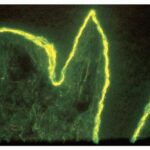

IF Testing. Examination of perilesional skin using DIF reveals linear deposition of complement at the basement membrane zone in the vast majority of cases. IgG is by far the most common immunoglobulin found, but IgM and IgA may be present as well. Increasing numbers of immunoglobulin subclasses noted at the dermal-epidermal junction favor a diagnosis of EBA over bullous pemphigoid. The presence of linear C3 at the dermal-epidermal junction alone favors bullous pemphigoid over EBA. However, use of routine DIF cannot reliably distinguish between bullous pemphigoid and EBA. IIF reveals circulating anti-basement membrane zone antibodies in up to 50%. |

The use of the salt-split skin technique leads to the appropriate diagnosis in most cases . The antibodies in EBA have specificity for the globular carboxyl terminus of type VII collagen and are deposited beneath the lamina densa. Therefore, on salt-split skin studies, IgG is on the floor and not on the roof of the split . |